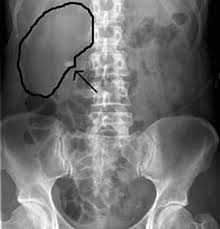

Kidney Stone X Ray Cost. 20 years experience radiology. When the stone is not on the focus the sound waves can damage the soft tissue of the kidney.

Ct kub ct scan kub kidney ureter bladder is ct scan of urinary system. Case studies case 1. Those kidney stones that are not visible on an x ray are usually detected on a ct scan.

Kidney stone cost 12k includes anesthesia laser work stent amount. Can u see kidney stones on x ray. My out of pocket costs were insignificant because my copays have always been very small. Those kidney stones that are not visible on an x ray are usually detected on a ct scan.